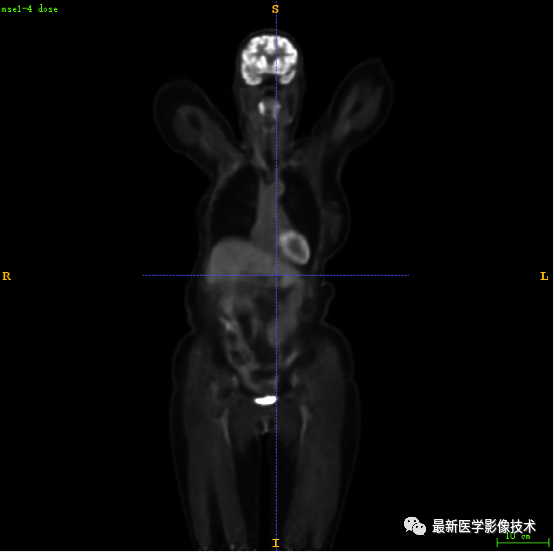

7.2、低剂量4重建结果

第一张是低剂量4的PET图像,第二张是full剂量PET图像,第三张是网络重建的PET图像。